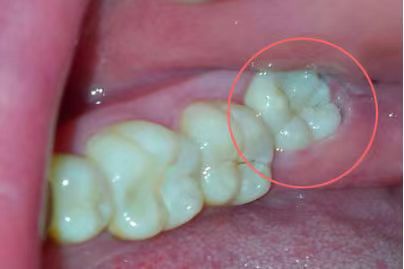

第二位患者同样姓张,但他在25岁的年纪,却已经被智齿疼痛折磨了2年多了。小张自述,自己的智齿疼,并不是“疼起来要人命”的那种,所以才一拖再拖。但近期,小张的下颌右侧牙龈反复长脓包,因担心病变扩大,才终于鼓足勇气走进了口腔科。医师在检查小张口内情况时看到,该患者下颌右侧第二磨牙牙冠表面完整,但在颊侧牙龈位置处,可见约5mm直径的脓包,脓包下,一颗牙冠倾斜部分微微露出的智齿隐约可见,而这两颗牙齿之间,竟有着大量嵌塞的食物,已然形成龋洞!并且第二磨牙周围骨质被破坏严重,牙齿已经是“悬浮”在牙槽窝内,这颗看似完整的牙齿因为智齿给予的阻力和龋洞的存在,其实已经不具有保留价值了,只能和智齿一起被连根拔除。